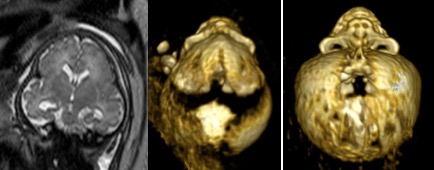

l’échographie 3D permet une étude fine du visage et montre un faciès caractéristique dans les craniosténoses impliquant la base et les craniofaciosténoses. elle permet également l’étude des autres organes en particulier les mains (Apert, Pfeiffer) et la face (craniofaciosténose).

le bilan doit être complet car on retrouve parfois des anomalies d’autres organes (coeur, reins, etc), dans le cadre d’associations syndromiques connues ou non (maladies orphelines) ; c’est en particulier le cas dans les trigonocéphalies (cf. ci-dessous).

différentes étiologies de trigonocéphalies syndromiques